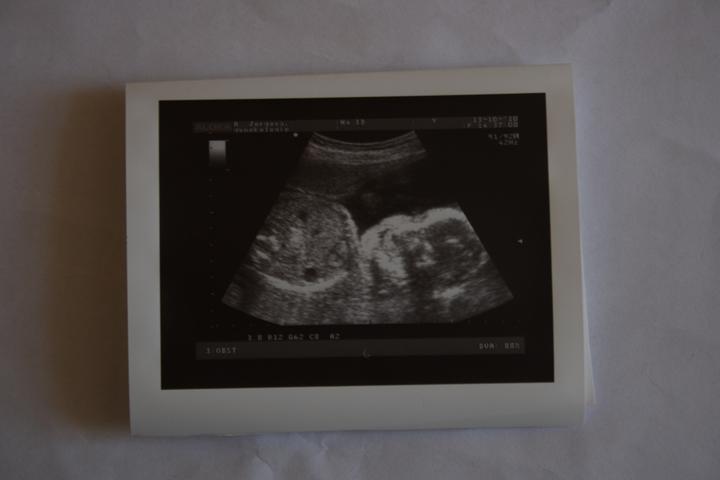

hcg 922...jsem těhotná 🙂